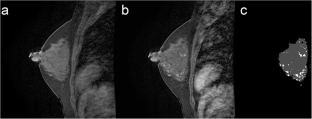

Fig. 4